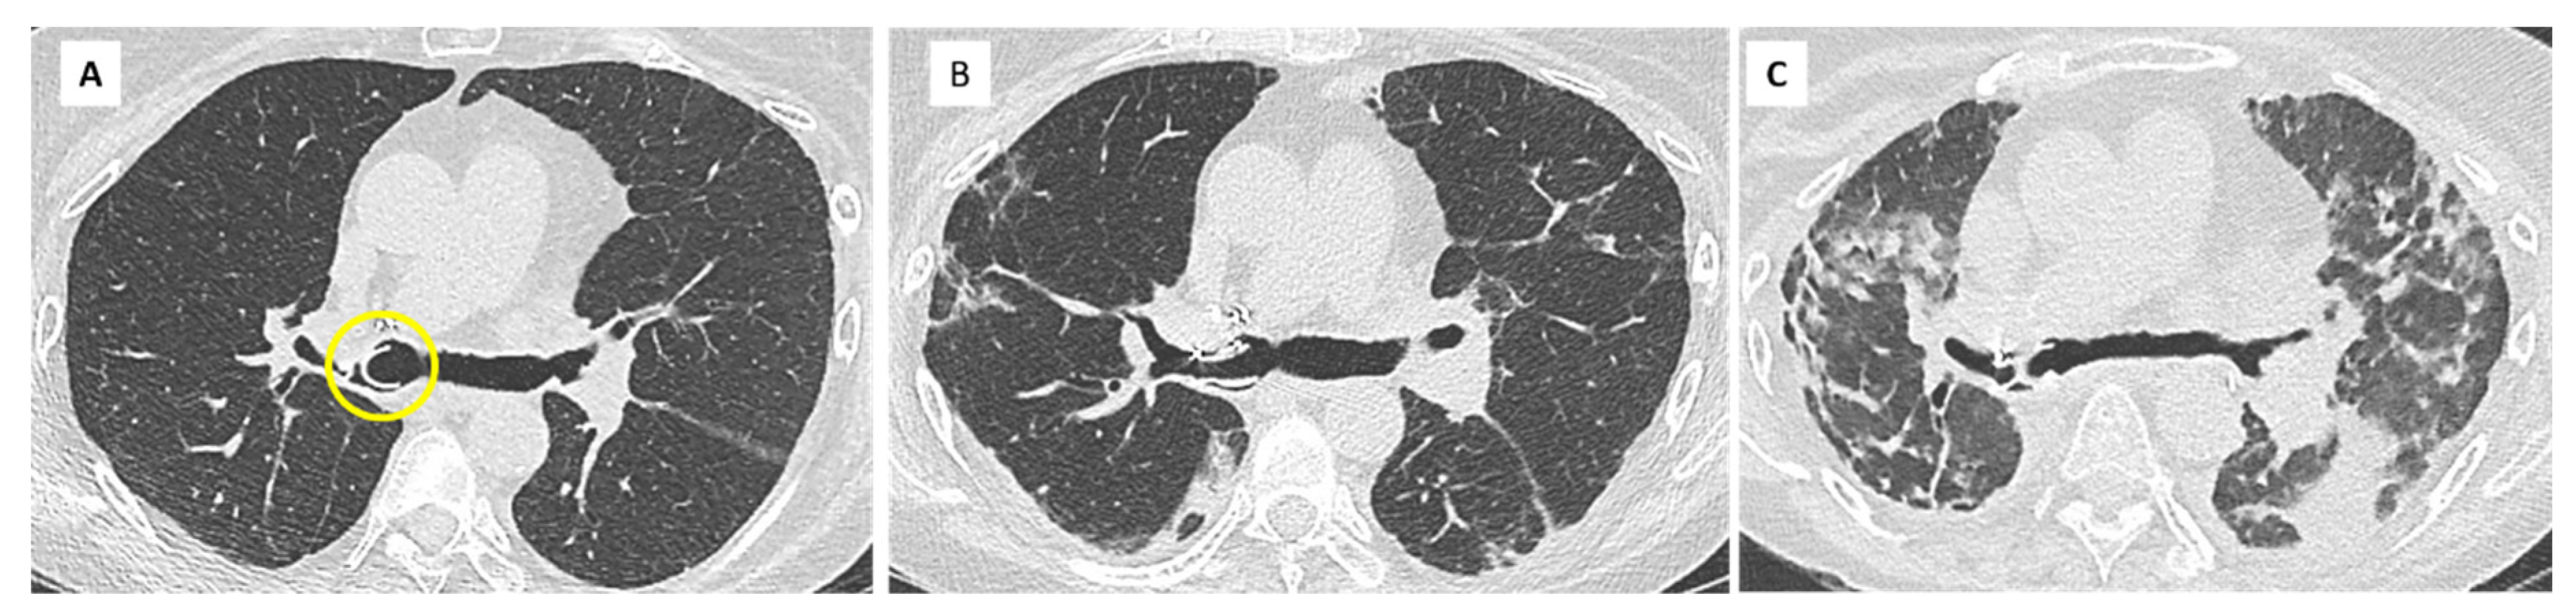

5. Restrictive Allograft Syndrome (RAS)